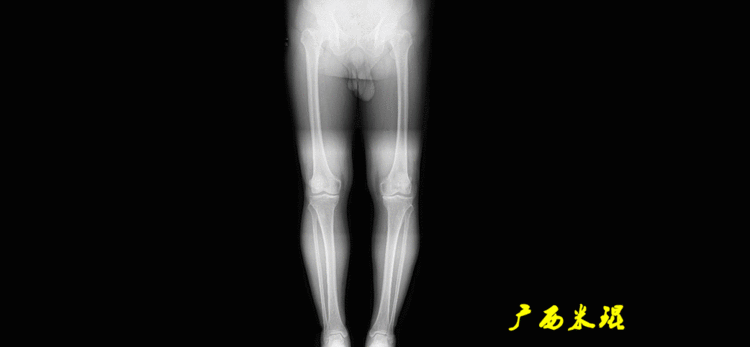

1、判定有无畸形下肢的畸形定义为生理轴线的偏移。关节角和轴线在冠状面、矢状面和横断面上可发生病理改变,并引起整个下肢的对线异常。

最常见的下肢畸形发生于冠状面,即膝内外翻畸形,冠状面的对线异常通过应用“对线异常检验”进行分析,机械轴的偏移(MAD)表现为对线异常。

膝内翻是指下肢力线通过膝关节中心点内侧,距中点2mm以上,偏内超过15mm为显著膝内翻。膝外翻是指下肢力线通过膝关节中心点外侧,距中点2mm以上,偏外超过10mm为显著膝外翻。

2、判断畸形的部位画出下肢全长片中的机械轴和力线轴,确定畸形来自股骨、胫骨还是关节内。首先我们确认股骨机械轴及mLDFA,超出范围为股骨畸形;然后我们确认胫骨机械轴及MPTA,超出范围为胫骨畸形;最后我们确认关节线的汇聚关系JLCA,超出范围为关节内畸形。